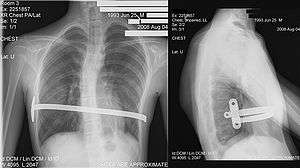

Pectus excavatum on PA chest radiograph with shift of heart shadow to the left and radioopacity of the right paracardiac lung field

Chest x-rays are also useful in the diagnosis. The chest x-ray in pectus excavatum can show an opacity in the right lung area that can be mistaken for an infiltrate (such as that seen with pneumonia).[22] Some studies also suggest that the Haller index can be calculated based on chest x-ray as opposed to CT scanning in individuals who have no limitation in their function.[23]

X-ray of a 15-year-old male after undergoing the Nuss procedure

Dr. Donald Nuss, based at Children's Hospital of The King's Daughters in Norfolk, Virginia, performed the first minimally invasive repair of pectus excavatum (MIRPE) in 1987[37] and presented it much later at a conference in 1997.[37][38][39] His procedure, widely known as the Nuss procedure, involves slipping in one or more concave steel bars into the chest, underneath the sternum. The bar is flipped to a convex position so as to push outward on the sternum, correcting the deformity. The bar usually stays in the body for about two years, although many surgeons are now moving toward leaving them in for up to five years. When the bones have solidified into place, the bar is removed through outpatient surgery.